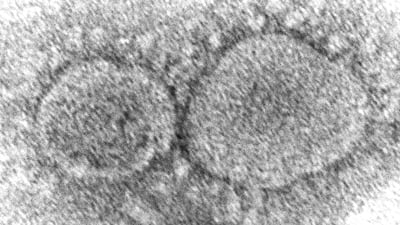

The CIA believes the virus responsible for the Covid-19 pandemic likely originated from a laboratory, according to an assessment released on Saturday that blames China while acknowledging that the spy agency has “low confidence” in its conclusion.

The finding suggests the agency believes the totality of evidence makes a lab origin more probable than a natural origin. However, the agency's assessment assigns a low degree of confidence to this conclusion, suggesting the evidence is deficient, inconclusive or contradictory.

Earlier reports on the origins of Covid-19 have split over whether the coronavirus emerged from a Chinese lab, potentially by mistake, or whether it arose naturally.

“CIA continues to assess that both research-related and natural origin scenarios of the Covid-19 pandemic remain plausible,” an official for the agency wrote about the agency's assessment.

Instead of new evidence, the conclusion was based on fresh intelligence about the virus's spread, its scientific properties and the work and conditions of China's virology labs.

While the origin of the virus remains unknown, scientists think the most likely hypothesis is that it circulated in bats, like many coronaviruses, before infecting another species, probably raccoon dogs, civet cats or bamboo rats. In turn, the infection spread to humans handling or butchering those animals at a market in Wuhan, where the first human cases appeared in late November 2019.

Some official investigations, however, have raised questions of whether the virus escaped from a lab in Wuhan. Two years ago a report by the Department of Energy concluded a lab leak was the most probable origin, though that report also expressed low confidence in the finding.